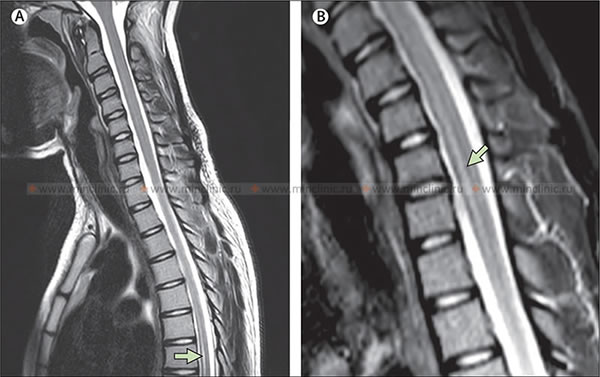

Магнитно-резонансная томография (МРТ) спинного мозга при миелите в результате вирусной инфекции Зика. A – МРТ позвоночника в Т2 режиме, показывающие усиление сигнала в грудном отделе Th5–Th8 (указано стрелкой) и увеличение шейного отдела спинного мозга. B - МРТ позвоночника в STIR режиме показывает усиление сигнала в шейном отделе спинного мозга C4–C7 (указано стрелкой).